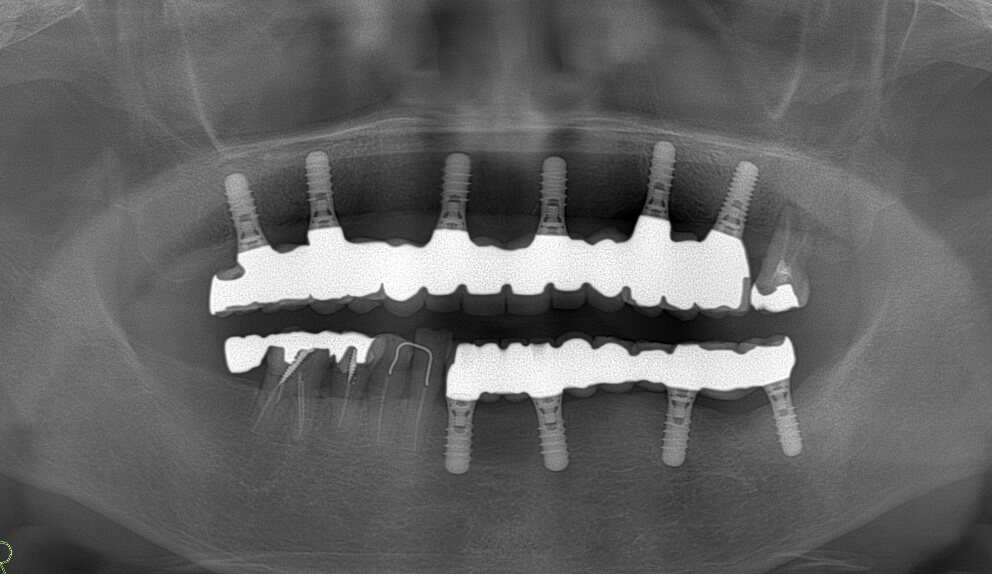

正確な診断を行うために、診断前に最先端歯科用CTでレントゲン撮影を行います。

インプラント治療には患者さまの精密な顎の骨の状態・状況を把握することが必要です。

インプラント相談会のCT撮影は完全無料です。

撮影したCT画像を見ながら、インプラント治療についてご納得いただけるまで丁寧にご説明いたします。